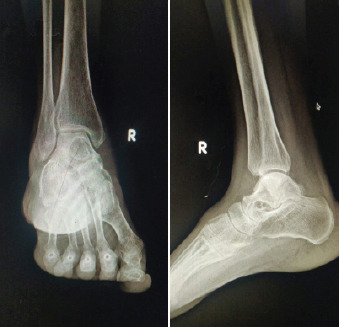

Figure 1.

(a and b) Anteroposterior and lateral view of ankle joint respectively showing lytic lesion in the talus.